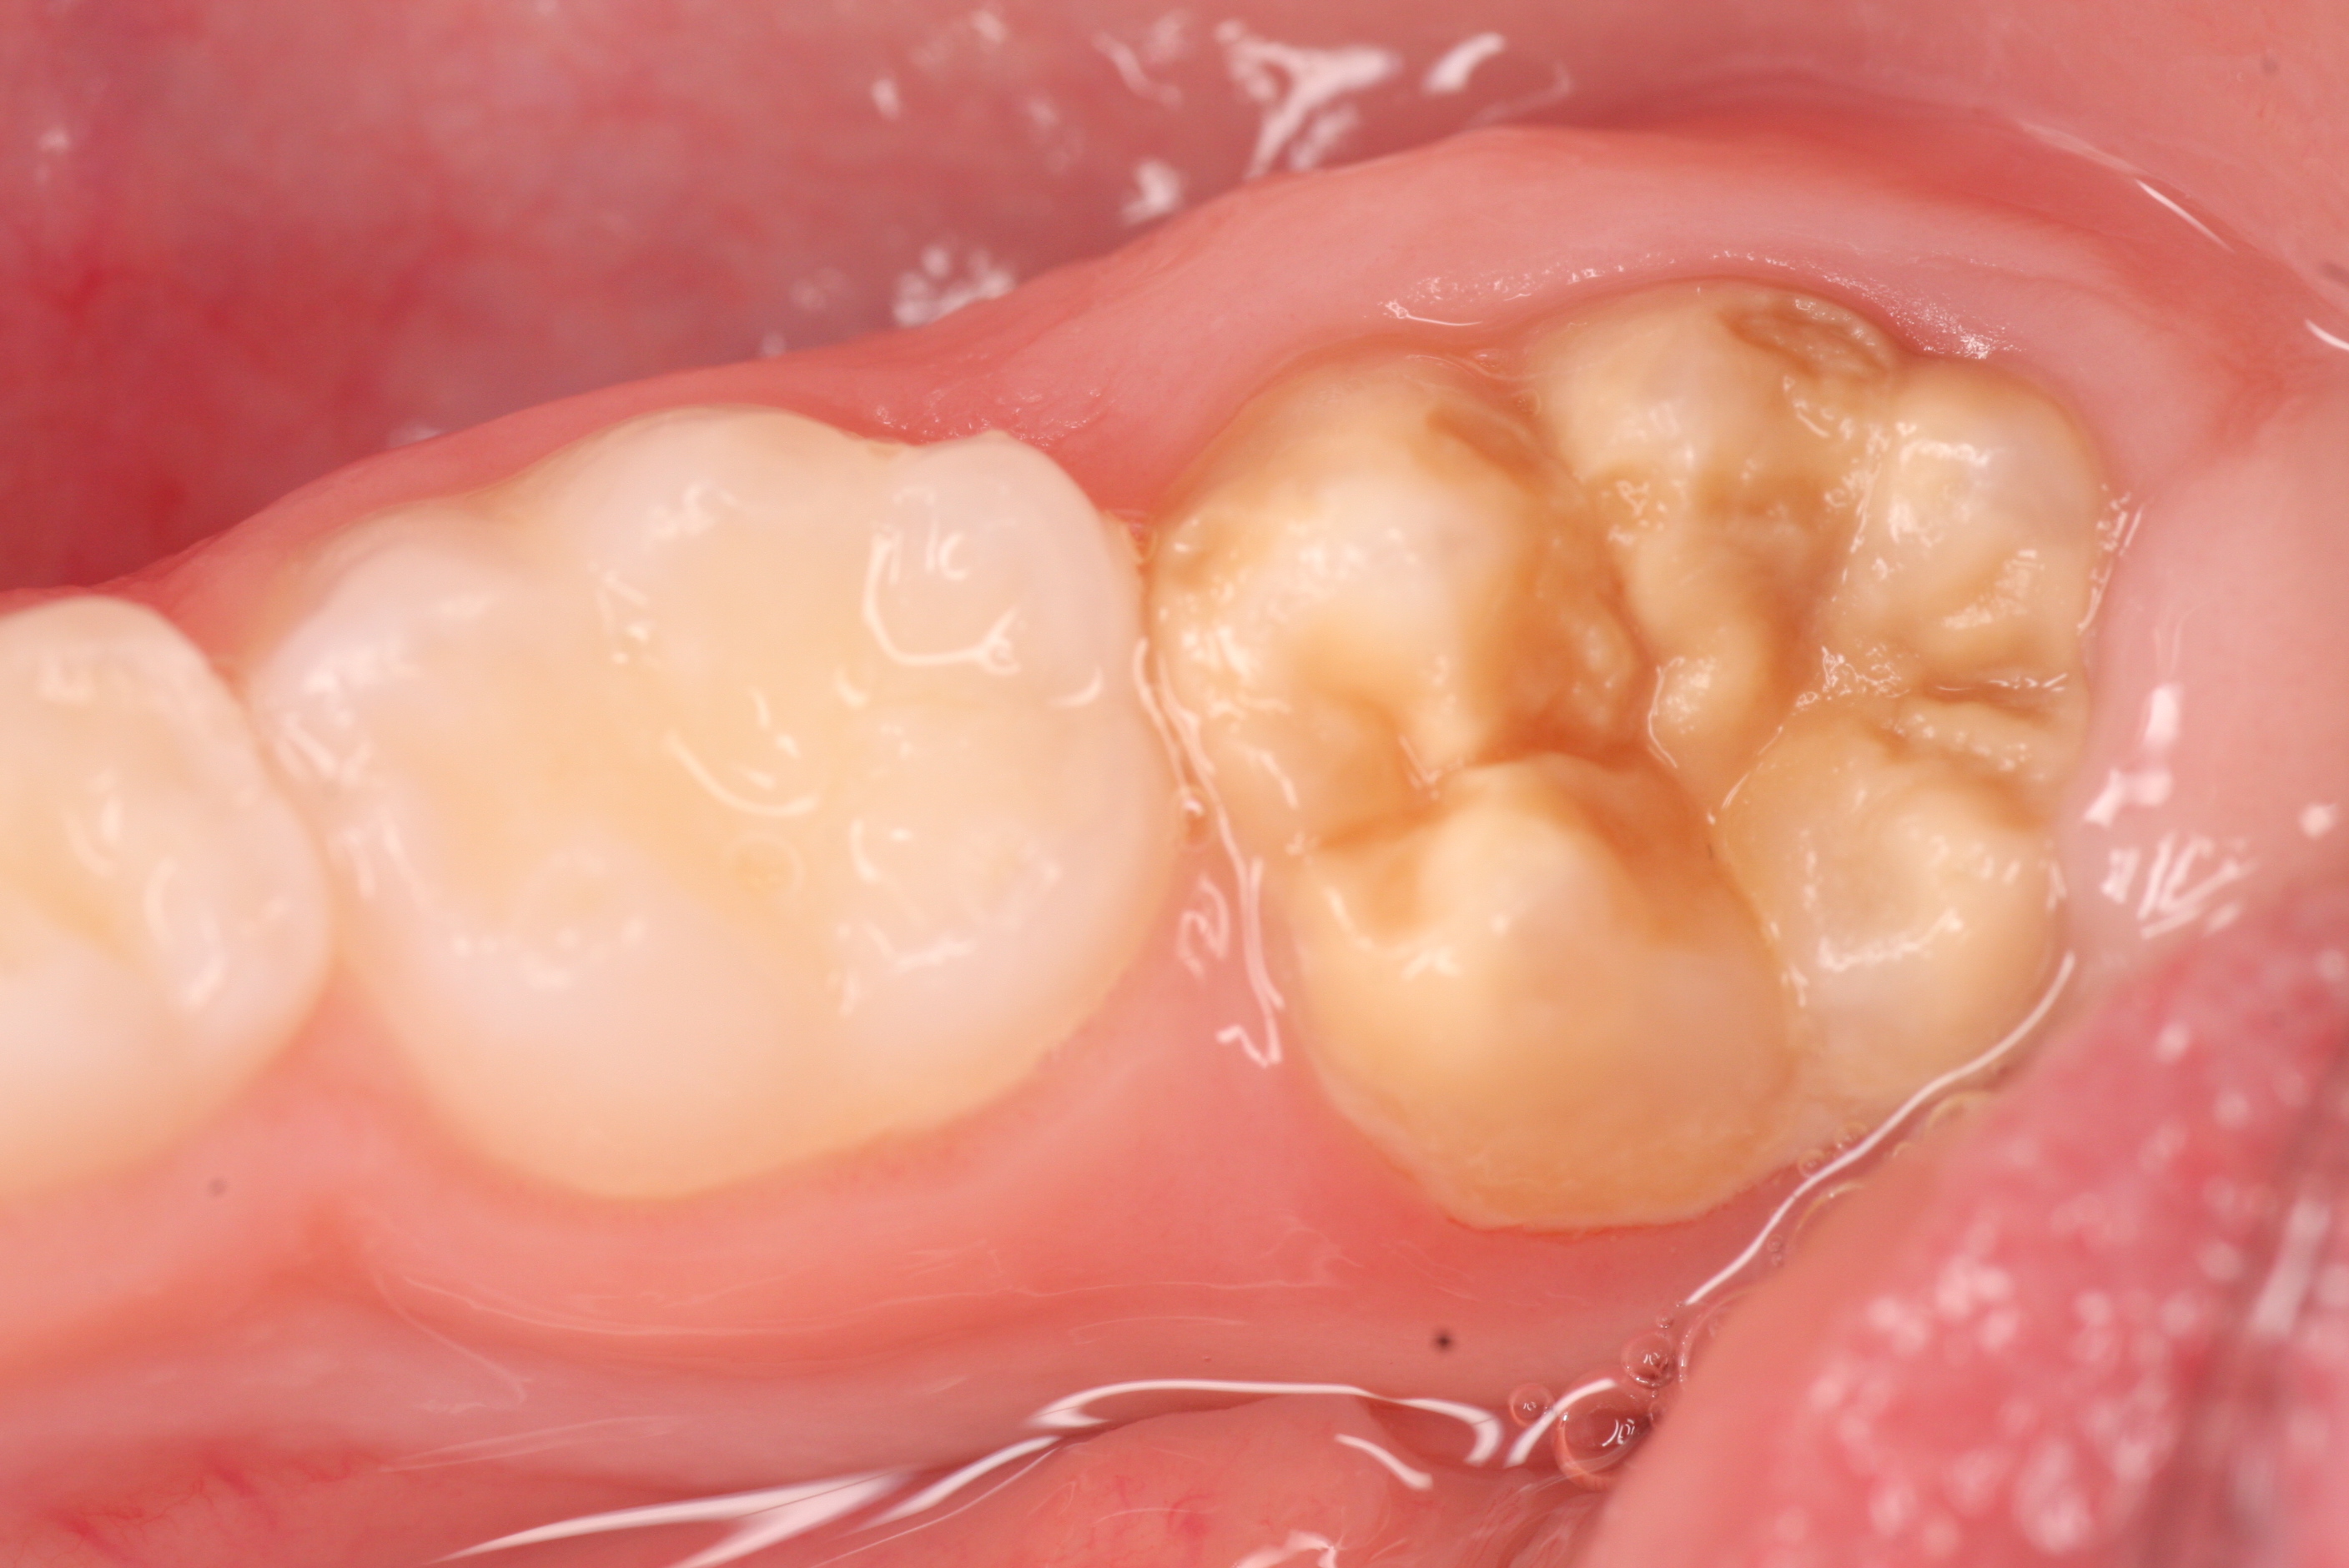

From www.dentistry33.com

Can the hypomineralization of enamel in deciduous cause the appearance Mih Dental Causes Molar incisor hypomineralisation (mih) is a developmental defect of enamel causing cream, yellow or brown opacities on. The cause is not fully known. Mih is a worldwide problem. Molar incisor hypomineralization (mih) is a significant health problem that can affect the child’s quality of life by negatively affecting their esthetics and function. Around 1 in 8 children in the uk. Mih Dental Causes.